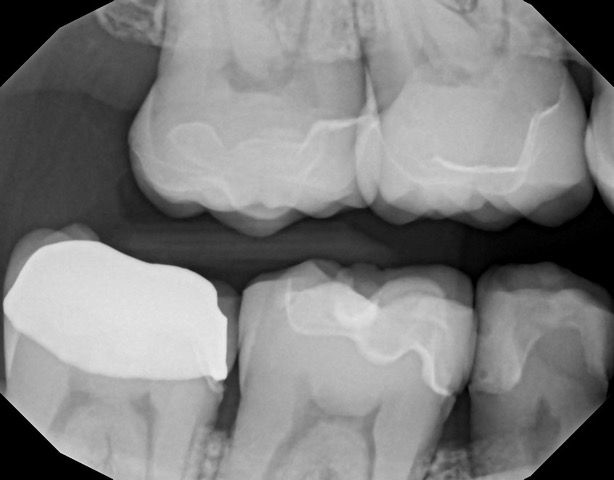

In my own practice, I compared two bitewings from the same patient, one taken with Acuity and one with our existing sensor, using identical exposure settings. The Acuity image immediately stood out. It showed noticeably sharper definition, cleaner contrast, and clearer interproximal visibility. The improvement was visible at a glance and reinforced the diagnostic advantages reported by our evaluators. This kind of image sharpness saves time and reduces retakes.